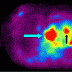

Anterior projection image of whole-body FDG-PET shows a large area of intense FDG uptake in the lower mediastinum (blue arrow). There is also a focus of intense activity in the left laryngeal region (red arrow). There is focal low-grade uptake at the right superior cardiac border, considered to represent physiologic uptake in the right atrium (green arrow). Physiologic uptake is noted in the ventricular myocardium (black arrow) and in the breasts (white arrows).

Lateral projection image of whole-body FDG-PET shows the focal increased FDG activity in the lower mediastinum (blue arrow) and in the neck (red arrow).